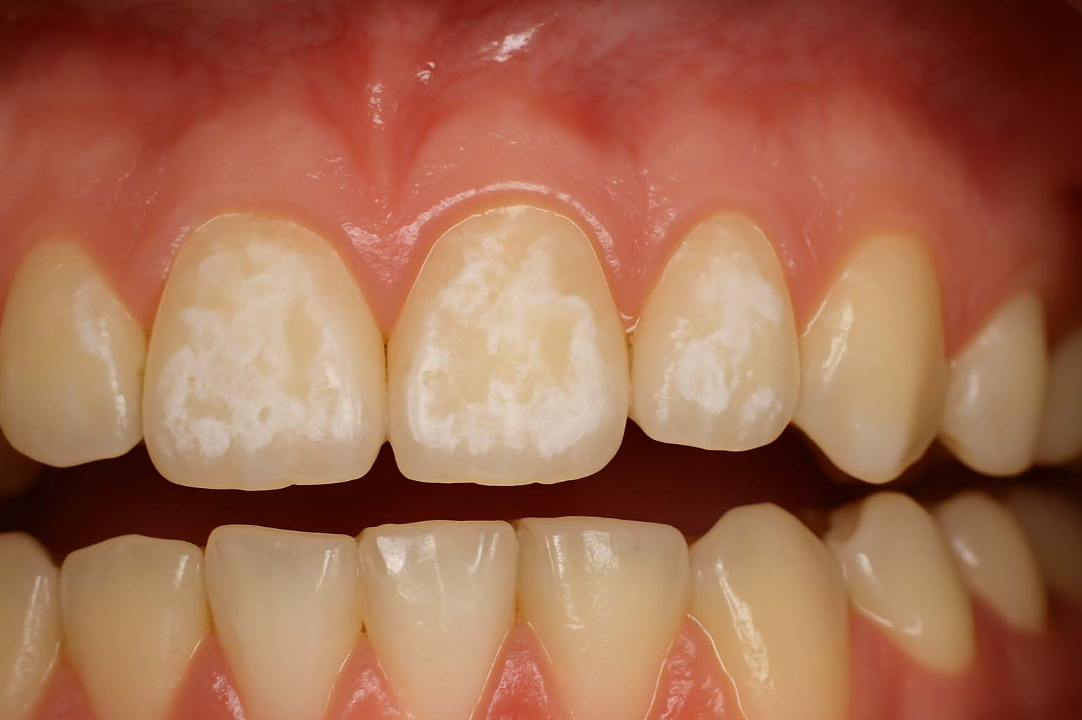

蛀牙前兆-牙齒脫鈣(圖片來源:Demineralization Of Teeth: Causes, Symptoms And Treatment Of Demineralization)

- 脫鈣是琺瑯質中的礦物質流失,常表現為霧面白斑或粉筆白。

- 原因多為牙菌斑長期附著、酸性環境使琺瑯質被溶解。

- 這類白斑通常偏霧面、粗糙,位置多在牙齦緣或矯正牙套附近。

- 若持續放著不處理,就會從輕微蛀牙惡化成真正的蛀洞。